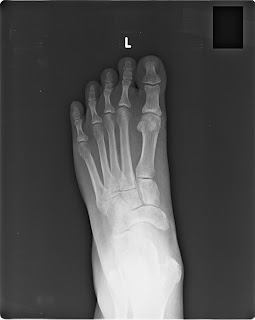

Xrays dated 5 June 2014 taken right after the fracture showing no ankle injury but only a fibula fracture and the opinion of three doctors including a radiologist and 2 orthopedics (Dr Shailza Aggarwal, and Dr Fahad and Dr Sandeep Chauhan) that there was no ankle injury and that the fibula fracture did not require surgery and would heal in a cast.

Xrays taken on 5 June 2014 the date of the fibula fracture